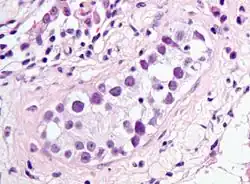

| Intratubular germ cell neoplasia. H&E stain. | |

GCNIS is not palpable, and not visible on macroscopic examination of testicular tissue. Microscopic examination of affected testicular tissue most commonly shows germ cells with enlarged hyperchromatic nuclei with prominent nucleoli and clear cytoplasm. These cells are typically arranged along the basement membrane of the tubule, and mitotic figures are frequently seen. The sertoli cells are pushed toward the lumen by the neoplastic germ cells, and spermatogenesis is almost always absent in the affected tubules. Pagetoid spread of GCNIS into the rete testis is common. Immunostaining with placental alkaline phosphatase (PLAP) highlights GCNIS cell membranes in 95 percent of cases. OCT3/4 is a sensitive and specific nuclear stain of GCNIS.[3]